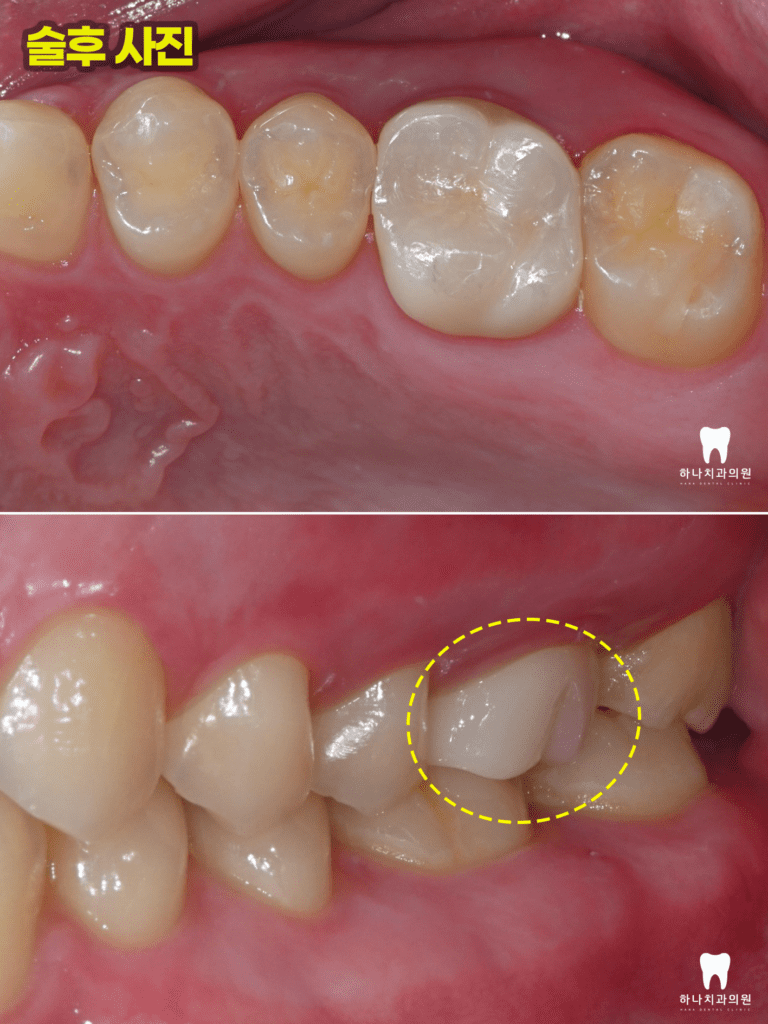

모든 치료를 마치고 난 후,

4년 뒤에도 전혀 문제를 발견할 수

없었고 주변 자연 치질과 조화로운 잇몸

기능을 유지하고 있는 것을 관찰하였습니다.